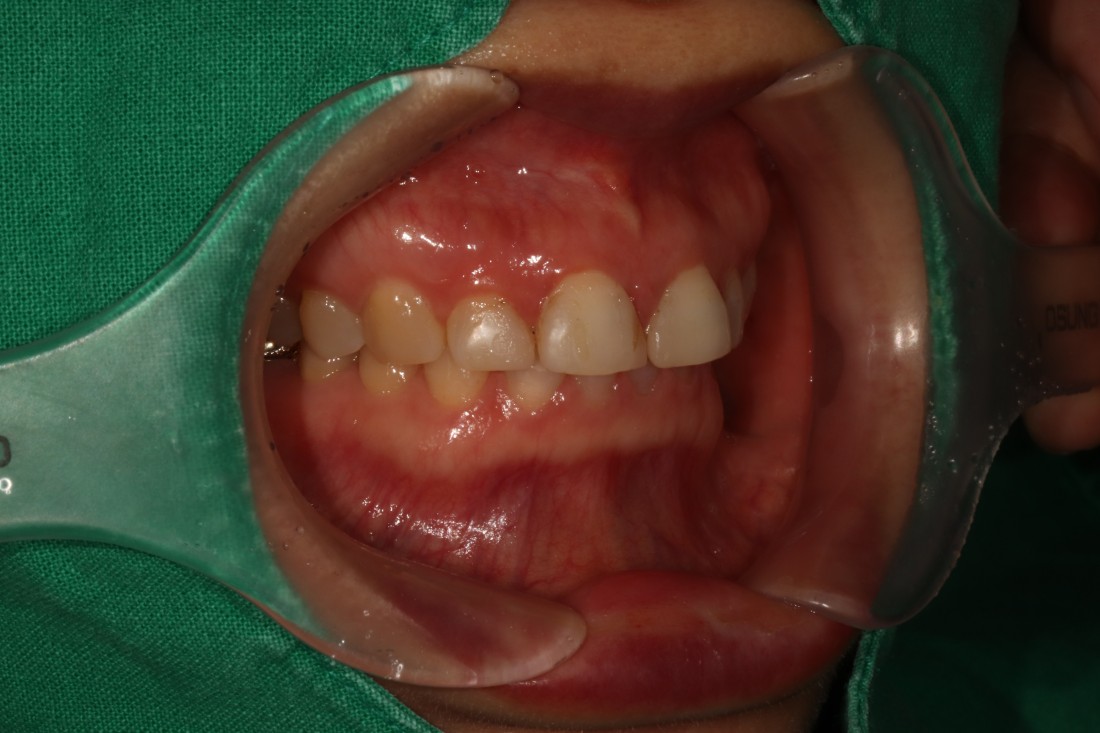

그렇지만 실제로 라미네이트 전/후 사례를

200케이스 가까이 공유하는

라미네이트 치과를 찾기는

쉽지 않은데요.

광주 무삭제 라미네이트 치과는

벌어진 앞니 / 깨진 앞니 /

얼룩덜룩한 앞니 / 왜소치 등

다양한 사례의 라미네이트 전-후 사진을

투명하게 공개하고 있습니다.